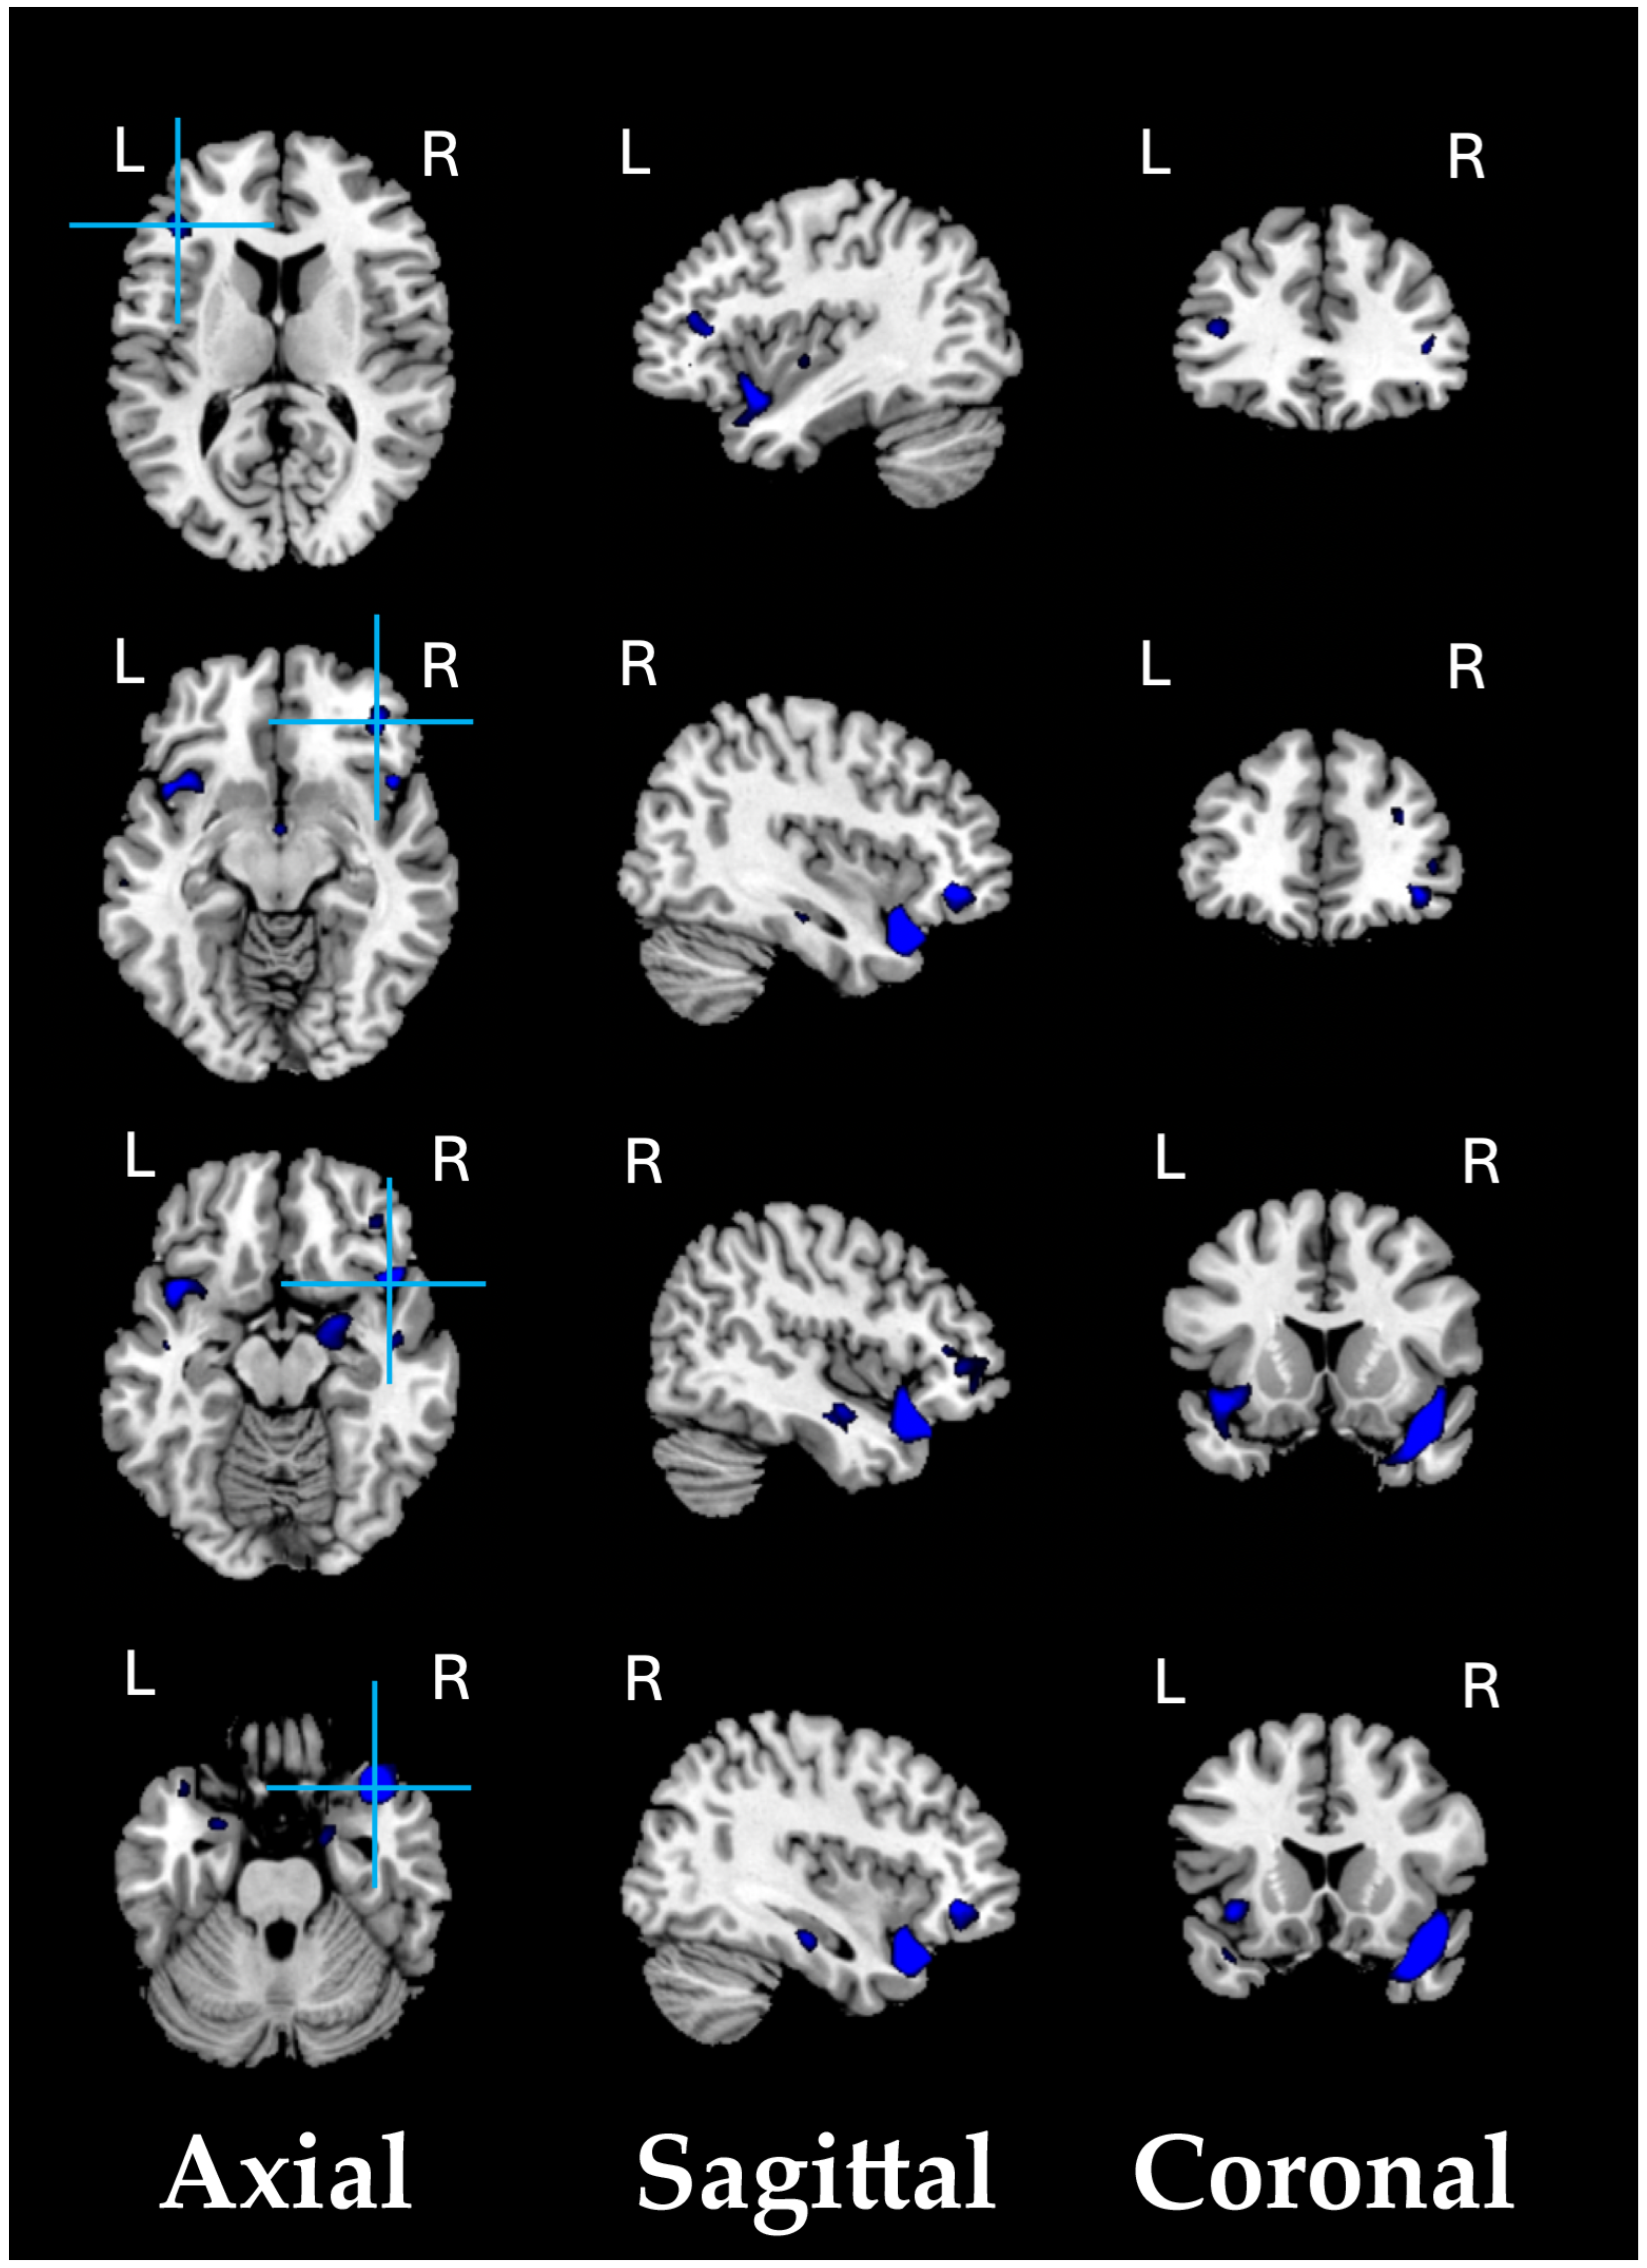

As a preliminary analysis, we conducted a structural VBM-GMV analysis on 74 SZ patients and 91 healthy controls. No significant effects of clinical covariates (i.e., age of onset, illness duration, and medication) on the whole-brain VBM-GMV values in SZ patients were found. A significant between-group difference (HC > SZ, i.e., GMV atrophy in patients) was observed, with t = 4.39, p = 0.00001 (FDR-corrected q < 0.001), Cohen’s d = 0.688. Figure 1 shows the significant GMV atrophy found in the brains of SZ patients, and Table 2 lists the corresponding MNI coordinates.

Figure 1.

Significant GMV atrophic regions in SZ patients compared to HCs (q < 0.001).

Compared with HC adults, SZ patients exhibited statistically significant (q < 0.001) lower VBM-GMV (i.e., atrophy) in the fronto-temporal and limbic regions.